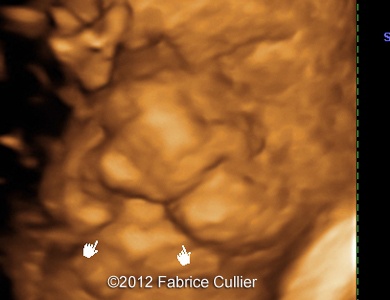

At 20 weeks, the sonographer found out a unilateral right cleft lip without other associated anomalies (Image 1-4).

Image 1-4: